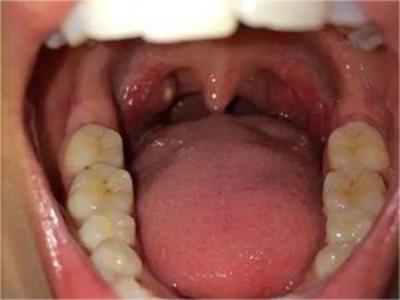

扁桃体

红肿 · 充血

淋菌性咽炎扁桃体肿大图

淋菌性咽炎患者的双侧扁桃体出现肿大样病变,扁桃体由于充血呈鲜红色,肿胀严重,超出双侧扁桃体弓范围。左侧扁桃体有几个粟粒大小的不规则白色脓点,伴有咽痛剧烈、口臭、发热等症状。